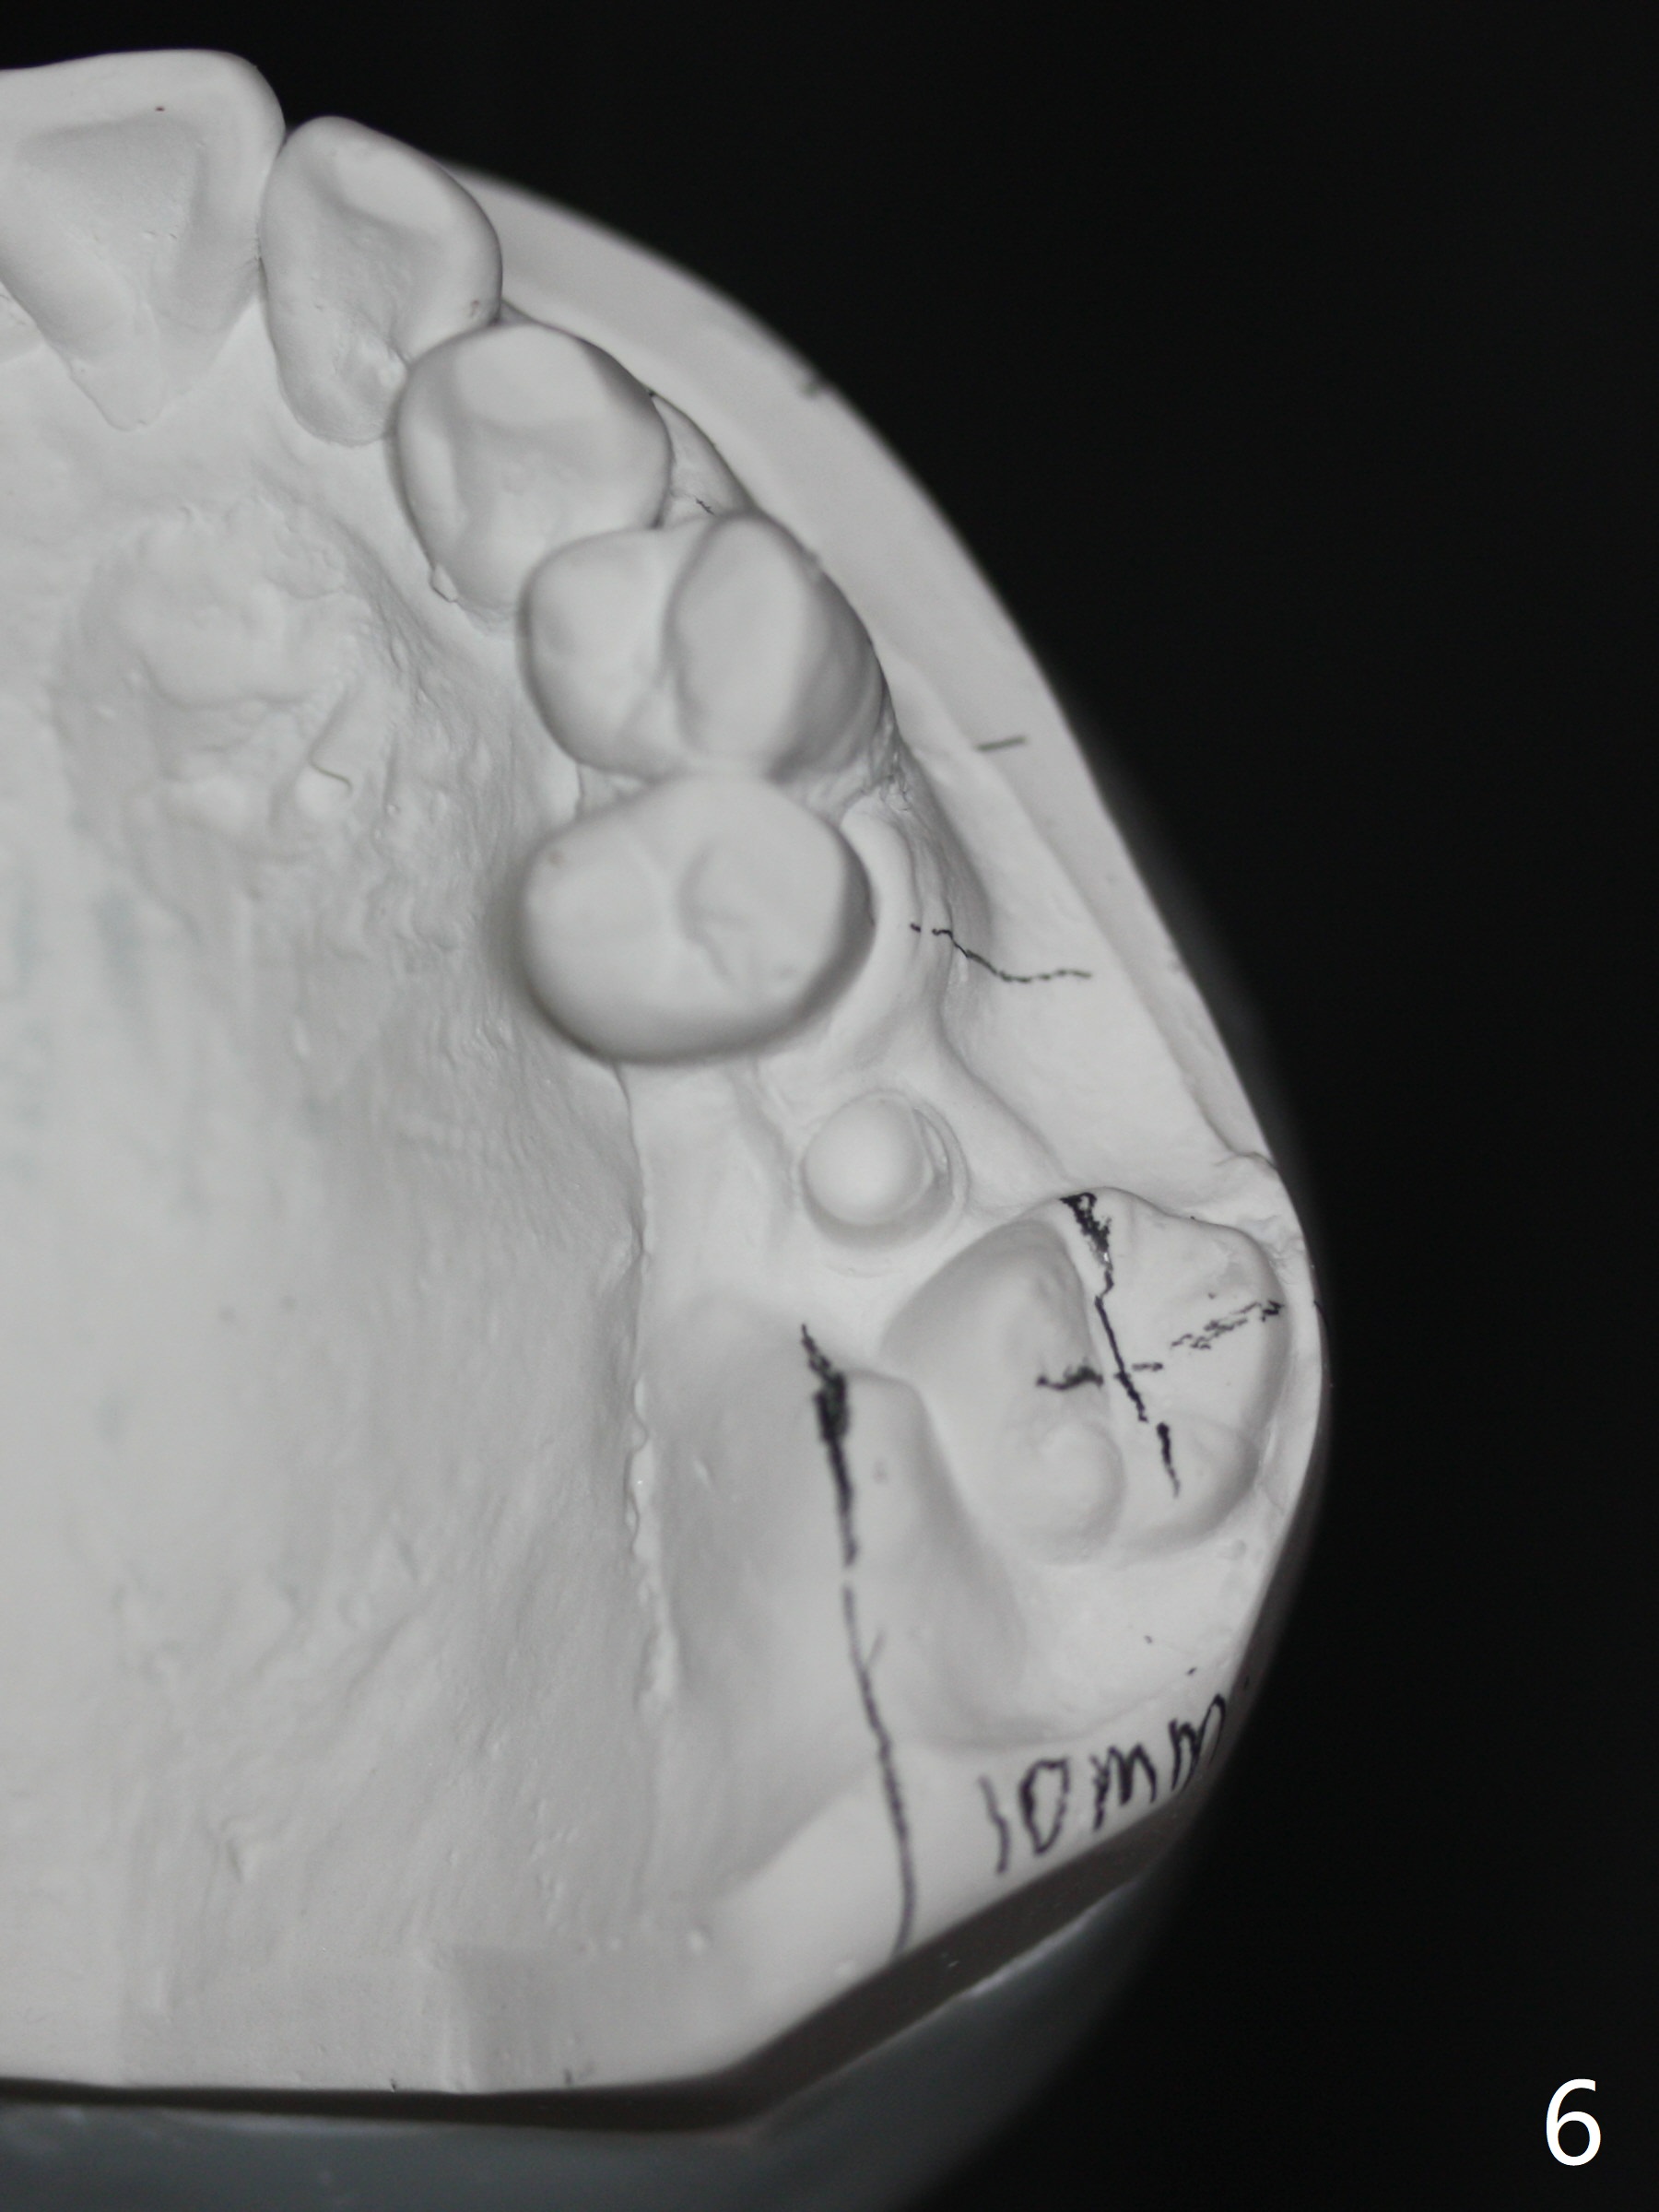

A 45-year-old man with normal facial profile (Fig.1-4) and malocclusion confined to UL quadrant (Fig.5-6) agrees with comprehensive orthodontic treatment. The implant threads at UL6 remain exposed 2 years 4 months postop. Thread exposure should disappears by distalizing UL5 and extruding UL8. Although upper wire sequence should be able to the limited malocclusion, extrusion of UL8 may use the lower arch as an anchor (elastic once a rectangular wire is installed, Fig.7,8).